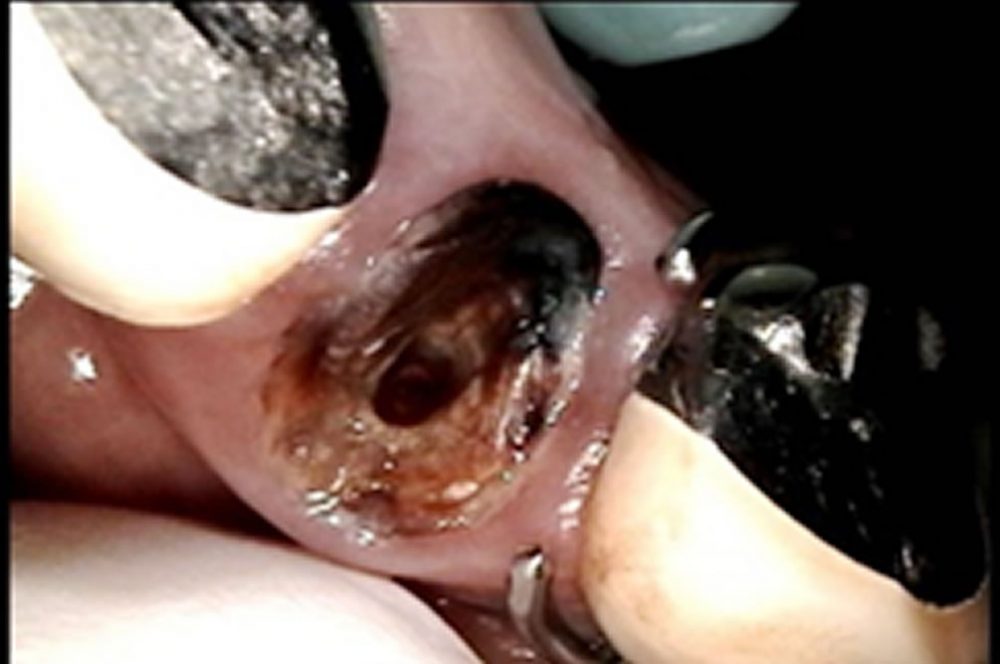

かぶせ物が取れた歯をセラミッククラウンで修復した症例

かぶせ物が取れた歯をセラミッククラウンで修復した症例 こちらの患者さまは左上のかぶせ物がとれたため、痛みはありませんが急患で来院されました。 レントゲンを撮り、主訴の左上3番周辺の状態も確認します。 当該歯は土台ごと外れ […]